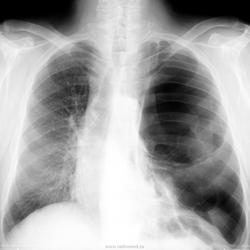

Мужчина за 60 лет. Лечится в хирургии по поводу обострения холецистита. Плановая ФГ грудной клетки. Особых жалоб нет. Говорит, что в детстве была травма...и что он знает, что одно легкое у него "темное".....

А мне кажется - не пневматоракс. На фоне раздутой легочной ткани прослеживаются какие-то элементы сосудистого рисунка.В диф ряд врождённую гипоплазию левой ветви легочной артерии,врождённую эмфизему левого лёгкого и прогрессирующую дистрофию (наименее вероятно,т.к. поражено одно лёгкое.

имхо: как-то картина со стороны левого лёкого, больше производит впечателение о буллёзных изменениях.Только встаёт вопрос-как это можно патогенетически связать с давней травмой?Нет ли в данном случае повреждения левого главного бронха (собственно говоря, тени левого главного бронха на снимке почему-то и не видно?) ( и лёгочных сосудов конечно) и не может ли так быть, что то что мы видим слева можно расценить,как буллёзную трансформацию сохранившейся части левого лёгкого, после повреждения главного бронха? Вообще картина левого лёгкого отдалённо напоминает "исчезающее лёгкое"(прогрессирующую лёгочную дистрофию), но вероятно, в данном случае механизм лёгочной дистрофии другой (травма).

Я за буллезные дела. Если бы это был пневмоторакс, то хочешь не хочешь пациент указал бы на какой - нибудь острый анамнез. А на рентгенограмме было бы видно поджатое легкое, а здесь его нет.

Спайки левой грудной полости, буллёзные изменения в лёгких или пневмоторакс . А по архиву что у него, Виктор Григорьевич?

Тотальные буллезные изменения левого легкого

Плюсую за врожденную патологию. Кистозная/кистозно-фиброзная гипоплазия, например.